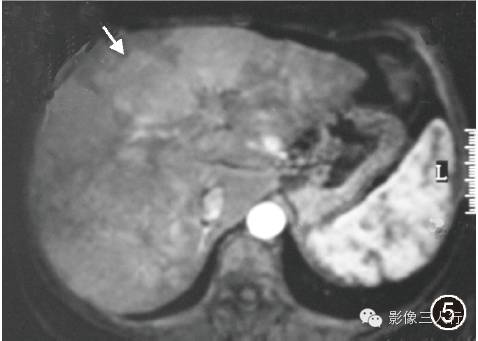

图5 MRI动态增强扫描动脉期像示病灶强化不明显,呈低信号(↑)